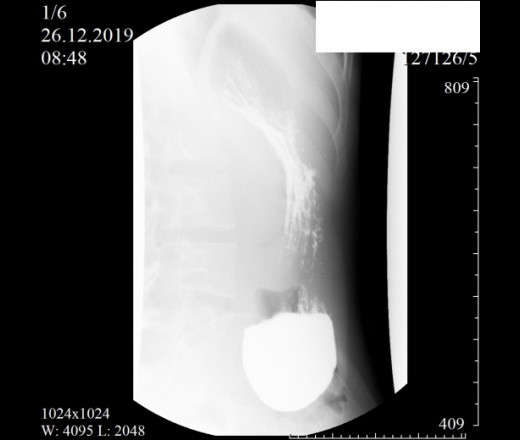

Девочка, 2004 г. Направлена с диагнозом ФНГ печени в онкоцентр. Приложены снимки рентгеноскопии ЖКТ. Помогите с интерпретацией, очень редко с этим работаем. Спасибо.

Как понимать аббревиатуру ФНГ? Не брался бы выность заключение после проведения Rg-скопии желудка, только по представленным снимкам. Можно однозначно сказать, что есть гипотония желудка( некотрые врачи используют термин гастроптоз).

PS С учетом избытка желудочного содержимого (впечатление, что в просвете не только жидкость, но и слизь), вялой перистальтики, можно подумть о хроническом гастрите. Не видя исследования вживую, всё только догадки.

"(красиво начали, жаль, оборвали) - гипотонус желудка, гипотонус луковицы ДПК, вероятный дуодено-гастральный рефлюкс, аорто-мезентериальная компрессия ДПК (стадия 1 или 2, не скажу - недостаточно снимков, скопию закончили рано), птоз тощей кишки и колоноптоз. "©